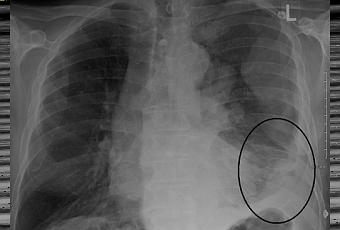

Mésothéliome siégeant dans la zone inférieure du poumon gauche.

Source iconographique et légendaire: https://commons.wikimedia.org/wiki/File:MesotheliomaCXR.png